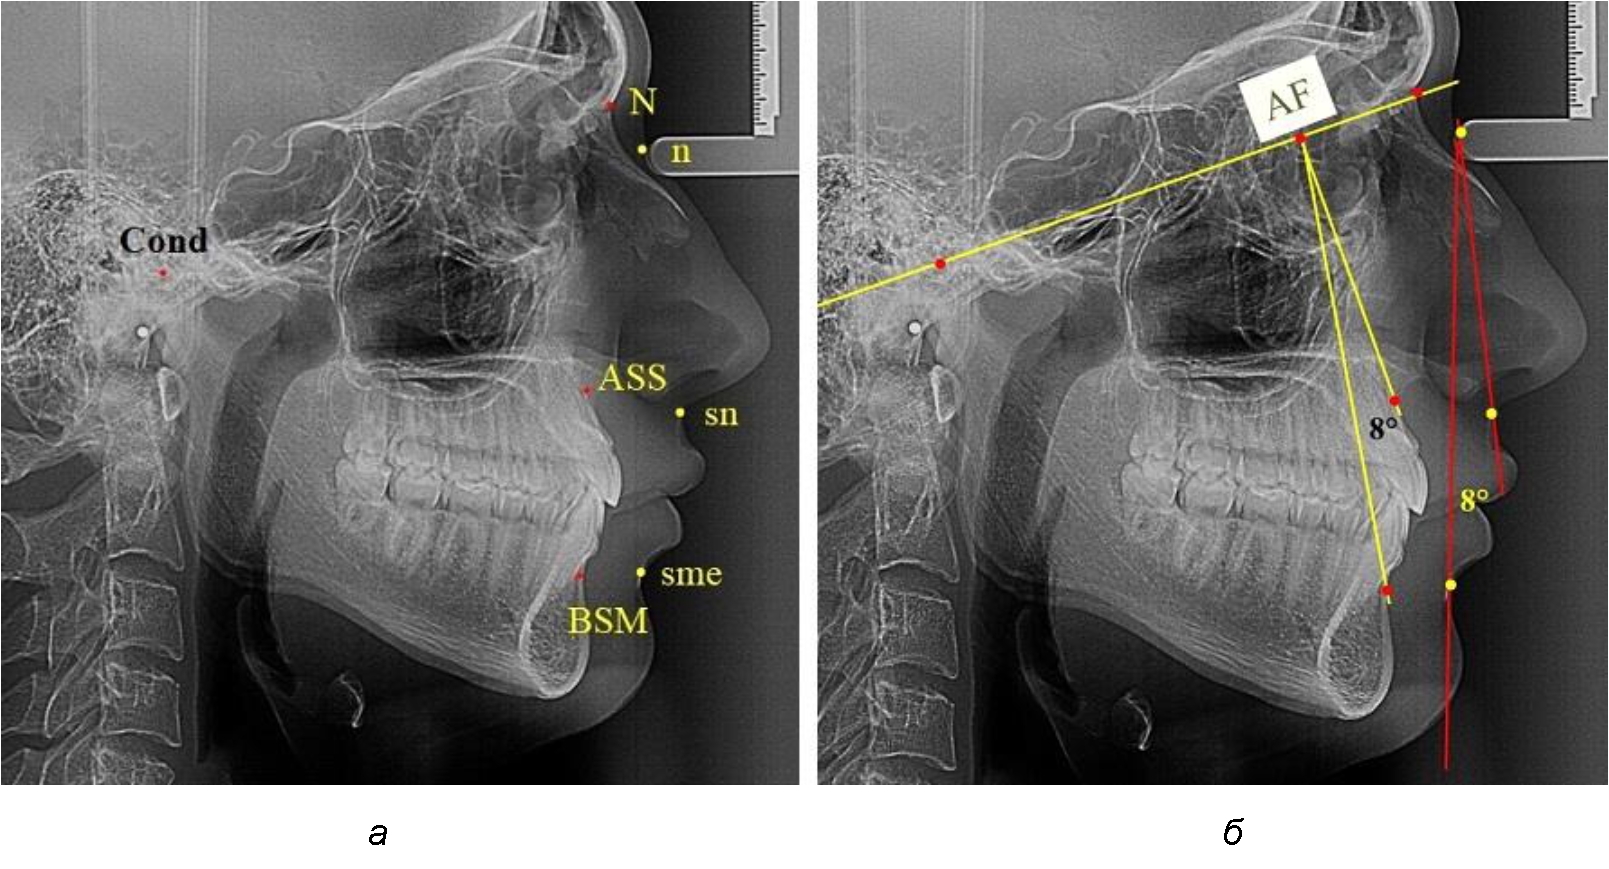

Лицевой межгнатический угол по кожным ориентирам строили соединением точек sn-n-sme, который обозначали как назально-супраменталь-ный угол (рис. 1).

Рис. 1. Точечные ориентиры (а) и основные линии (б) боковой ТРГ для анализа параметров лицевого межгнатического угла

Для построения лицевого межгнатического угла по костным ориентирам использовали в качестве основного ориентира кондилярно-назальную линию, соединяющую точки Cond (верхняя точка суставной головки) и N (место соединения лобной и назальных котей). На передней поверхности челюстей, в наибольшей вогнутости переднего контура, отмечали апикальные точки Downs (ASS и BSM). Из субспинальной точки Downs верхнего апикального базиса ASS строили перпендикуляр к линии Cond–N. Место пересечения линий определяло положение конструктивной апикально-фациальной точки, которую обозначали литерами AF. Точку AF соединяли с супраментальной точкой Downs (BSM) нижнего апикального базиса. Таким образом, костный лицевой межгнатический угол обозначали как угол ASS–AF–BSM. Для определения типов нижней челюсти оценивали величину нижнечелюстного угла. В исследовании выделяли группы людей с нейтральным, вертикальным и горизонтальным типами, которые влияли на положение нижней челюсти.